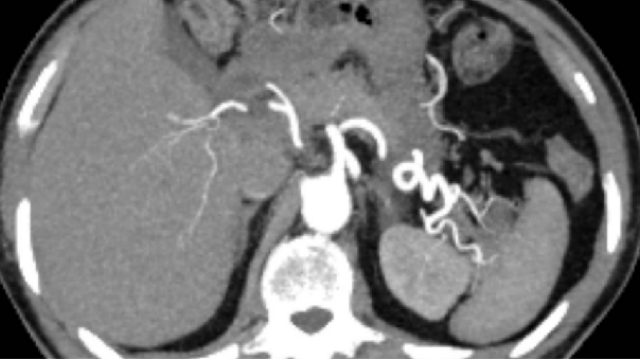

專(zhuān)注于通過(guò)微創(chuàng)技術(shù)保留膽囊功能并取出結(jié)石,為膽囊功能良好的患者提供新選擇。該方案采用直視下取石操作,確保結(jié)石取盡并降低殘留風(fēng)險(xiǎn),同時(shí)避免傳統(tǒng)膽囊切除可能引發(fā)的消化功能影響。針對(duì)不同病情需求,可靈活選擇聯(lián)合術(shù)式:例如膽囊結(jié)石合并膽總管結(jié)石時(shí),采用內(nèi)鏡下括約肌切開(kāi)術(shù)(EST)聯(lián)合保膽取石術(shù),或術(shù)中同期完成保膽取石與膽總管探查一期縫合,實(shí)現(xiàn)多部位結(jié)石同步處理。微創(chuàng)技術(shù)是優(yōu)勢(shì),需2-3個(gè)微小切口,手術(shù)時(shí)間縮短且出血量少,患者術(shù)后當(dāng)天即可下床活動(dòng),住院周期壓縮至3-5天。雙鏡聯(lián)合(腹腔鏡+膽管鏡)等創(chuàng)新術(shù)式進(jìn)一步提升了操作**性,依托影像準(zhǔn)確定位減少組織損傷,并通過(guò)術(shù)中監(jiān)測(cè)降低并發(fā)癥概率。需強(qiáng)調(diào)的是,該方案需嚴(yán)格評(píng)估適應(yīng)癥——膽囊收縮功能正常且無(wú)嚴(yán)重病的患者更適用,術(shù)后需配合飲食調(diào)整及藥物輔助(如熊去氧膽酸)以管理復(fù)發(fā)風(fēng)險(xiǎn)。當(dāng)前技術(shù)成熟度持續(xù)提升,新型硬質(zhì)內(nèi)鏡設(shè)備與取石器械的研發(fā)為臨床實(shí)踐注入新動(dòng)力,推動(dòng)成功率與患者滿意度雙增長(zhǎng)。浙江立體化保膽取石解決方案收費(fèi)術(shù)后需定期復(fù)查并調(diào)整生活習(xí)慣,維持膽汁代謝平衡。

通過(guò)微創(chuàng)技術(shù)保留膽囊功能,避免傳統(tǒng)切除后可能出現(xiàn)的消化問(wèn)題。現(xiàn)代手術(shù)采用腹腔鏡或膽道鏡操作,需2-3個(gè)小切口即可完成,術(shù)中出血量少,術(shù)后當(dāng)天患者可下床活動(dòng),住院時(shí)間縮短至3-5天。針對(duì)不同患者需求,方案涵蓋藥物、內(nèi)鏡干預(yù)及手術(shù)取石等多種方式,其中內(nèi)鏡逆行胰膽管造影(ERCP)等技術(shù)可定向處理結(jié)石。中西醫(yī)結(jié)合模式進(jìn)一步優(yōu)化了圍手術(shù)期管理,中藥輔助調(diào)節(jié)膽汁成分并降低復(fù)發(fā)風(fēng)險(xiǎn),推動(dòng)個(gè)體化**進(jìn)程。值得注意的是,“兩孔法”微創(chuàng)技術(shù)為招飛、空乘人員及特殊職業(yè)群體提供了符合體檢要求的解決途徑,兼顧功能保留與外觀需求。目前腹腔鏡聯(lián)合膽道鏡的雙鏡探查成為主流術(shù)式,能夠評(píng)估膽囊狀況并靈活調(diào)整手術(shù)策略,提升操作可靠性。該方案要求患者術(shù)后定期隨訪,配合飲食調(diào)整與生活方式干預(yù),以實(shí)現(xiàn)膽囊健康的長(zhǎng)期維護(hù)!通過(guò)腹腔鏡聯(lián)合膽道鏡直視操作,完整取出結(jié)石并降低復(fù)發(fā)風(fēng)險(xiǎn)。